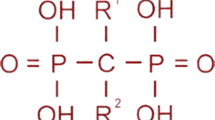

Bisphosphonates (BPs) are stable derivatives of inorganic pyrophosphate in which two phosphate groups are covalently linked to carbon group. They bind hydroxyapatite crystals and inhibit osteoclast activity. The affinity for bone matrix is conferred by the hydroxyl groups attached to the central carbon (R1 position) and by the adjacent phosphate groups, while potency for bone resorption is determined by the final structural fraction (in the R2 position). Based on the presence or not of nitrogen or amino groups in the R2 position, BPs can be classified as non–nitrogen-containing (first-generation BPs) or nitrogen-containing (second- and third-generation BPs). In first-generation BPs, a cytotoxic analog of adenosine triphosphate accumulates in osteoclasts and leads to cell death, whereas nitrogen-containing BPs promote osteoclast apoptosis inhibiting the activity of farnesyl pyrophosphate synthase. Skeletal retention of BPs depends on availability of hydroxyapatite binding sites [63]. BPs are hydrophilic medications with low gastrointestinal absorption, high distribution volume and renal excretion. After a rapid clearance from the circulation there is a long elimination phase due to a slow release from bone tissue [64]. This feature differentiates BPs from other antiresorptive drugs such as denosumab and makes side effects such as rebound hypercalcemia less likely. BPs have been used in children, following the evidence of efficacy in adults. Pamidronate, neridronate, and zoledronic acid are available for intravenous (IV) use, while alendronate and risedronate are available for oral administration. Most of the safety and efficacy reports concerning BPs in pediatric populations have been derived from studies on patients with OI.